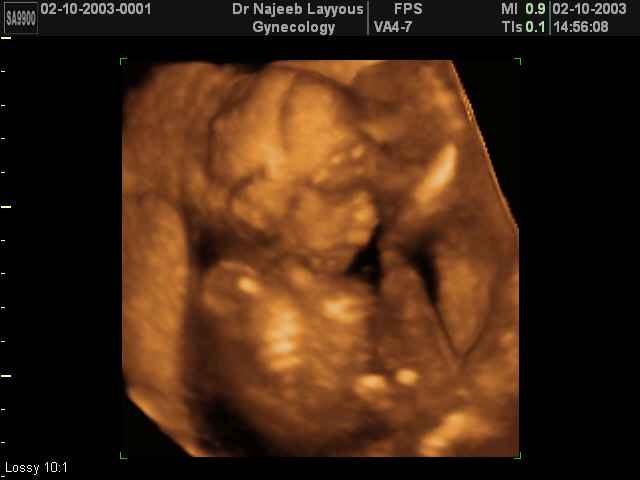

3D second trimestre échographie Photos de numérisation - deuxième partie de la grossesse | Dr N Layyous

3D second trimestre échographie Photos de numérisation - deuxième partie de la grossesse